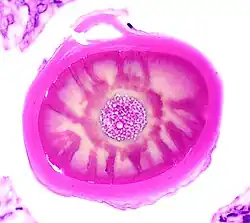

Histology of a multilayered corpus amylaceous of the prostate.